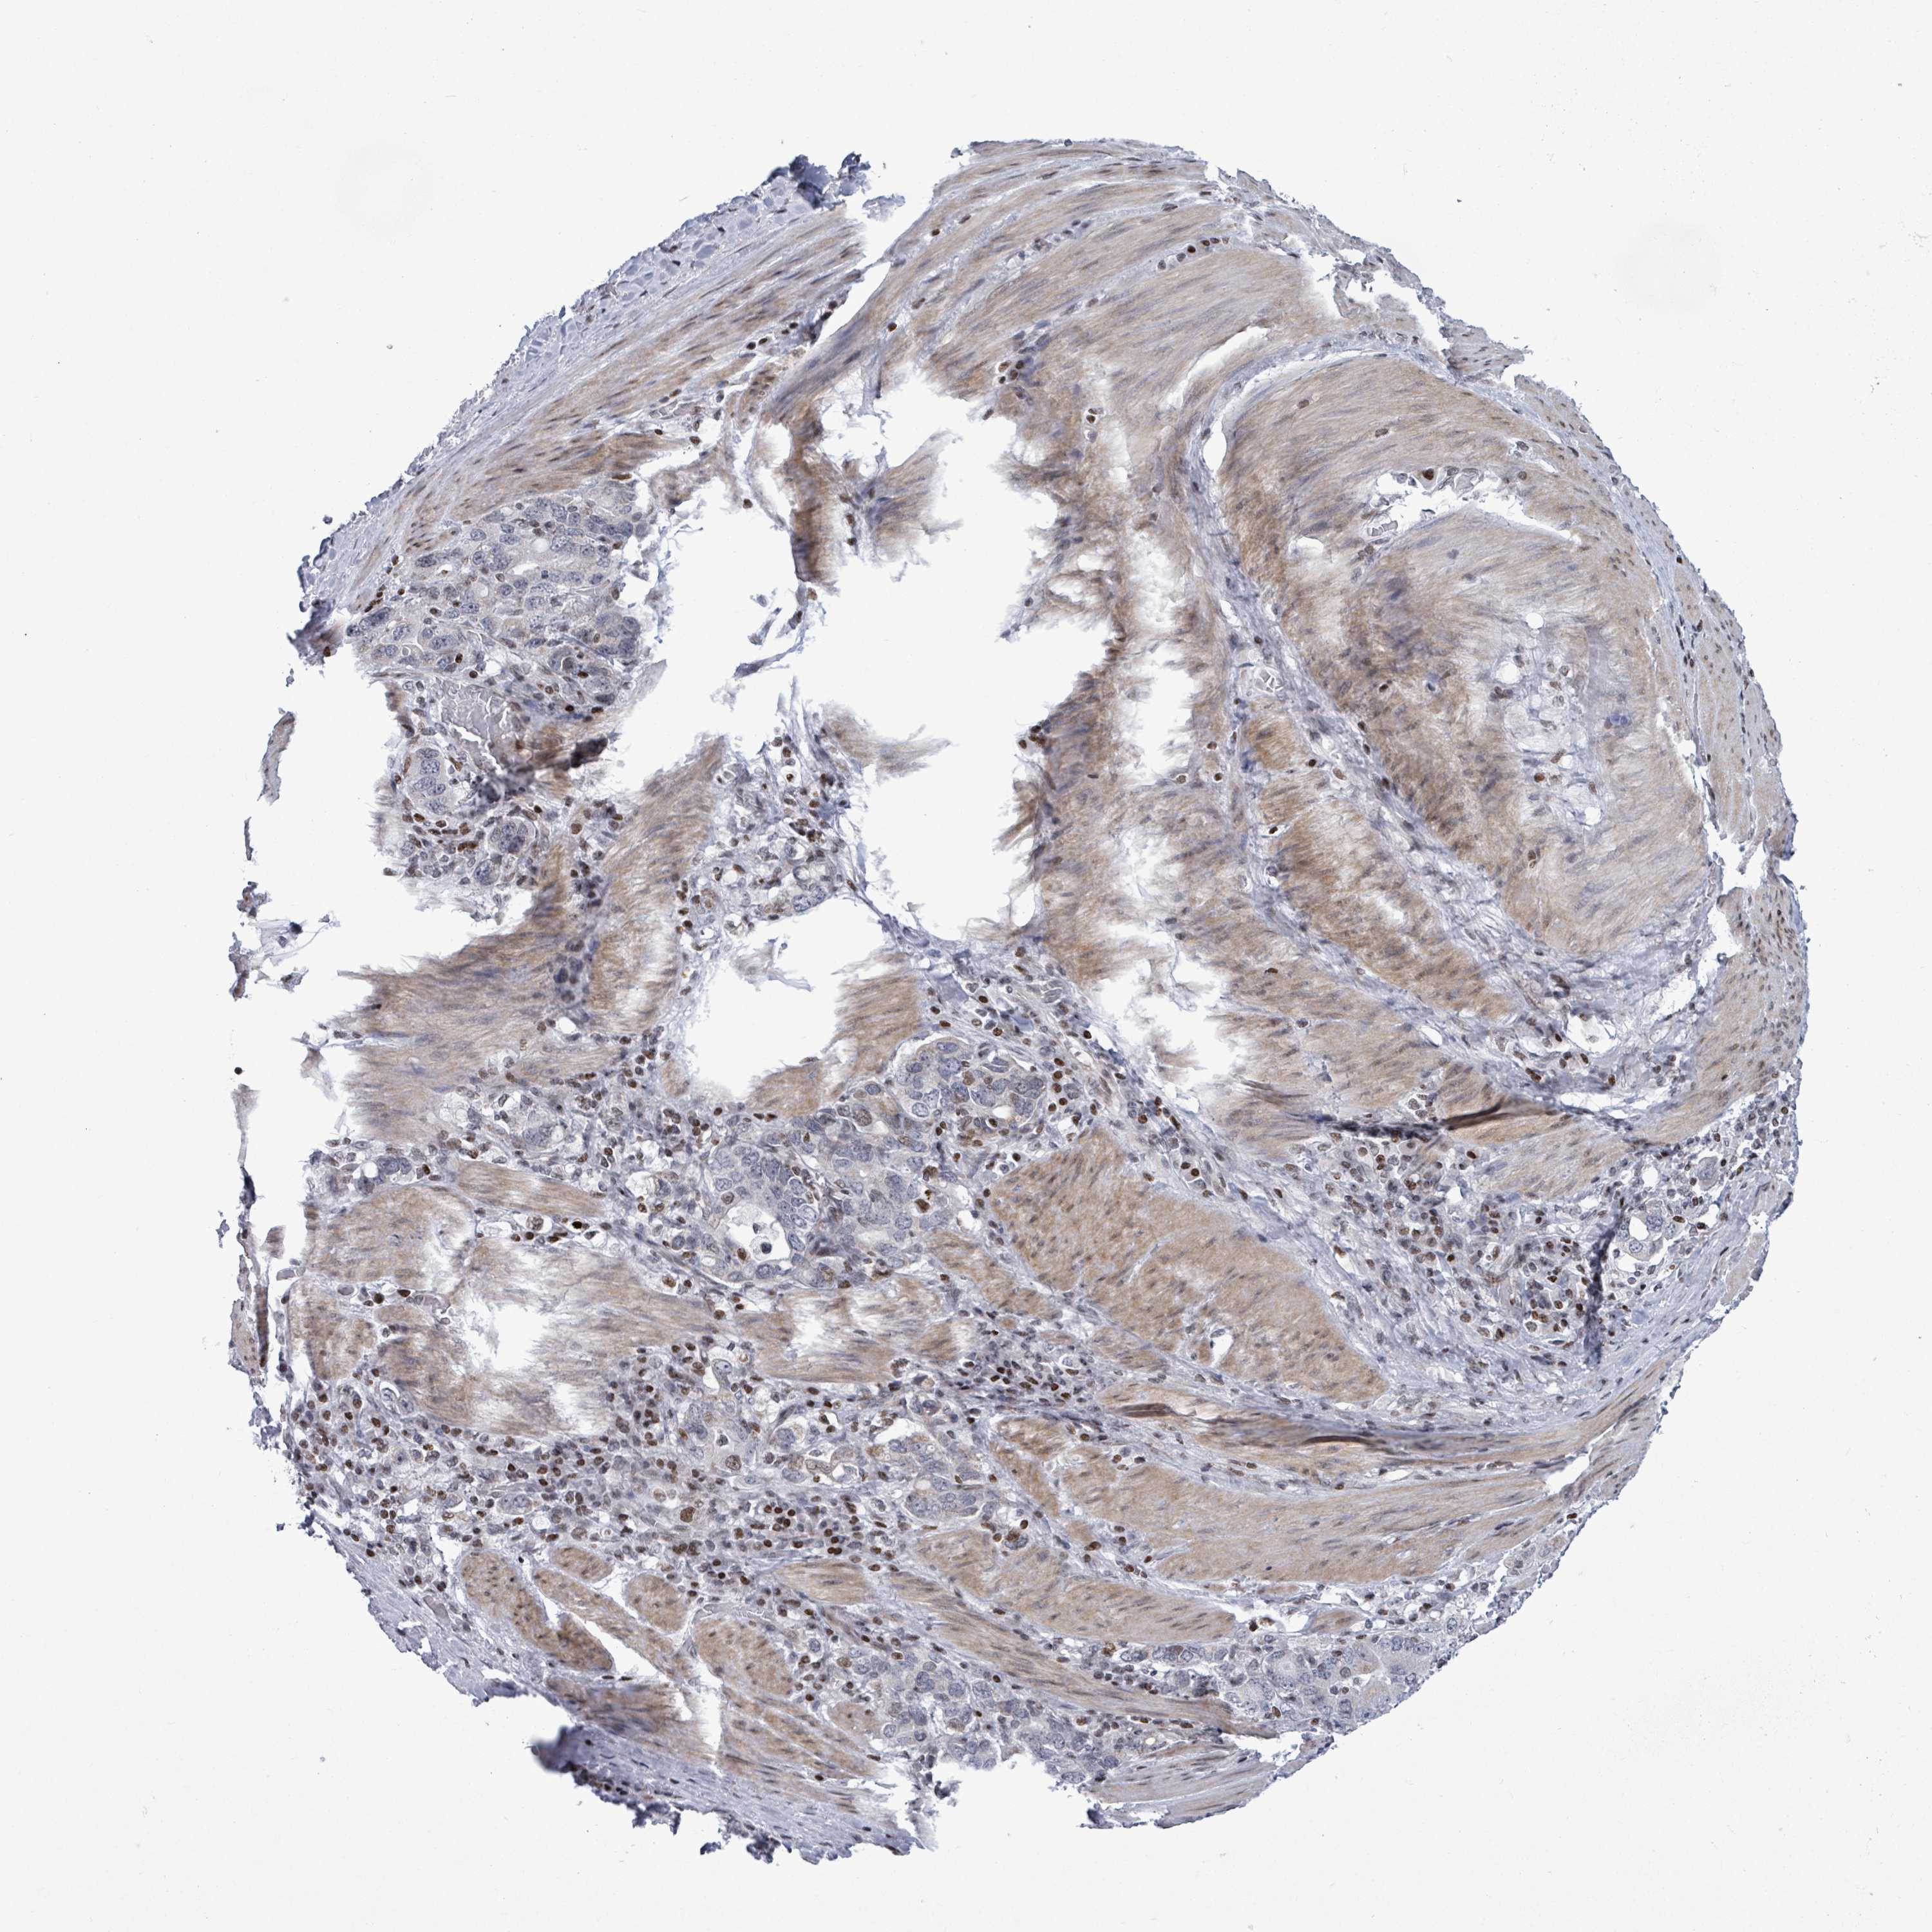

STOMACH CANCER - Protein expressioni

A mouse-over function shows sample information and annotation data. Click on an image to view it in a full screen mode. Samples can be filtered based on level of antibody staining by selecting one or several of the following categories: high, medium, low and not detected. The assay and annotation is described here.

Note that samples used for immunohistochemistry by the Human Protein Atlas do not correspond to samples in the TCGA dataset.

Antibody stainingi

Antibody staining in the annotated cell types in the current human tissue is reported as not detected, low, medium, or high, based on conventional immunohistochemistry profiling in selected tissues. This score is based on the combination of the staining intensity and fraction of stained cells.

Each image is clickable and will lead to virtual microscopy that enables deeper exploration of all samples and also displays staining intensity scores, fraction scores and subcellular localization as well as patient and tissue information for each sample.

Antibody HPA051804

Antibody HPA063581

Staining

High

Medium

Low

Not detected

Adenocarcinoma, NOS